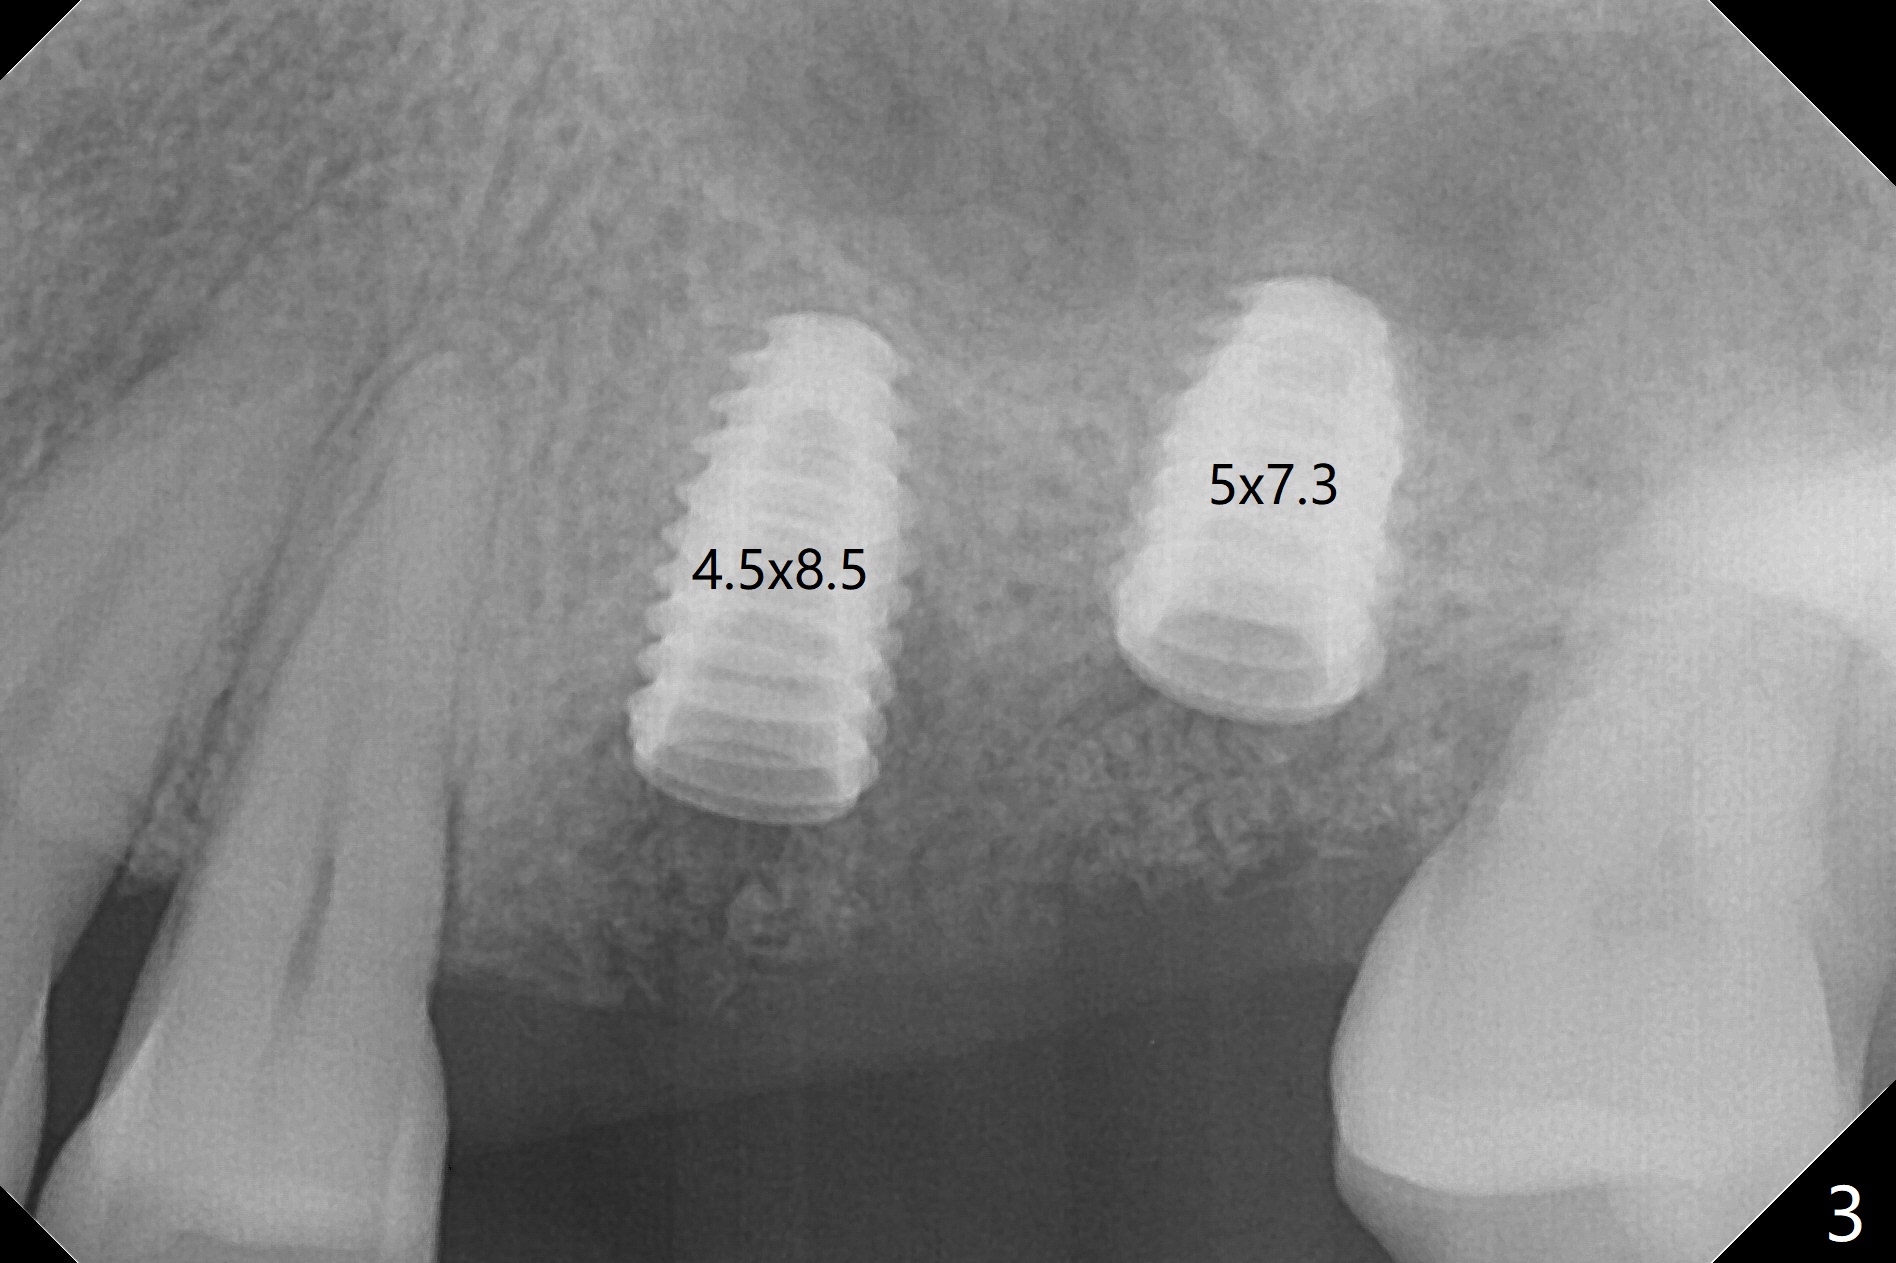

After placement of a 4.5x8.5 mm implant at #13, a vertical anchor pin is used, which is helpful for #14 osteotomy (Fig.1-3). One hand is free. Sinus lift with 2.8 mm reamer is not efficient, since it is difficult to feel stopper. A 5x7.3 mm implant has to be removed from the site of #14 for use of Magic Expanders from 3.0 to 4.3 mm at the depth of 13 mm (gingival level). Autogenous bone harvested from osteotomy is used for sinus lift. It appears that the implants are placed deep; healing abutments with 5 mm cuff are placed (Fig.4 (extraoral bitewing)).